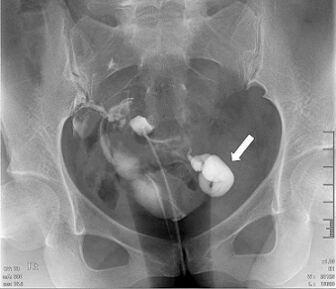

73.34歲女性子宮輸卵管攝影檢查呈現如圖,箭號所指之病灶,下列何者為最恰當之診斷? (A)輸卵管積水(hydrosalpinx) (B)子宮(輸卵管)外孕 (C)輸卵管惡性腫瘤 (D)子宮內膜異位